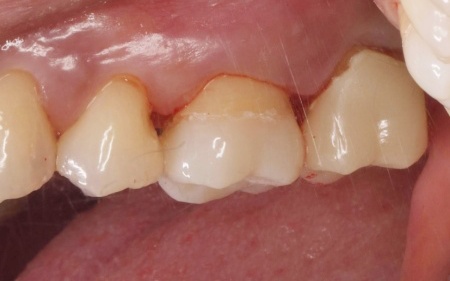

| 行ったご提案・治療内容 | 患者様は噛む力が非常に強く、その影響でエナメル質が割れてしまっています。 そこで詰め物の素材には、自費診療の白い素材「セラミック」の中でも、人工ダイヤモンドと呼ばれるほど強度があり、審美性にも優れている「ジルコニア」を選択しました。 すべての詰め物にジルコニアを用いるのが理想でしたが、ジルコニアは費用が高額です。 詰め物の形状には、歯の溝や一部を補う小さな詰め物「インレー」と、歯の噛む面を広範囲で覆う「アンレー」があります。 まずはメタルインレーをすべて外し、詰め物を装着するために歯の形を整え、型取りを行います。 |

治療後